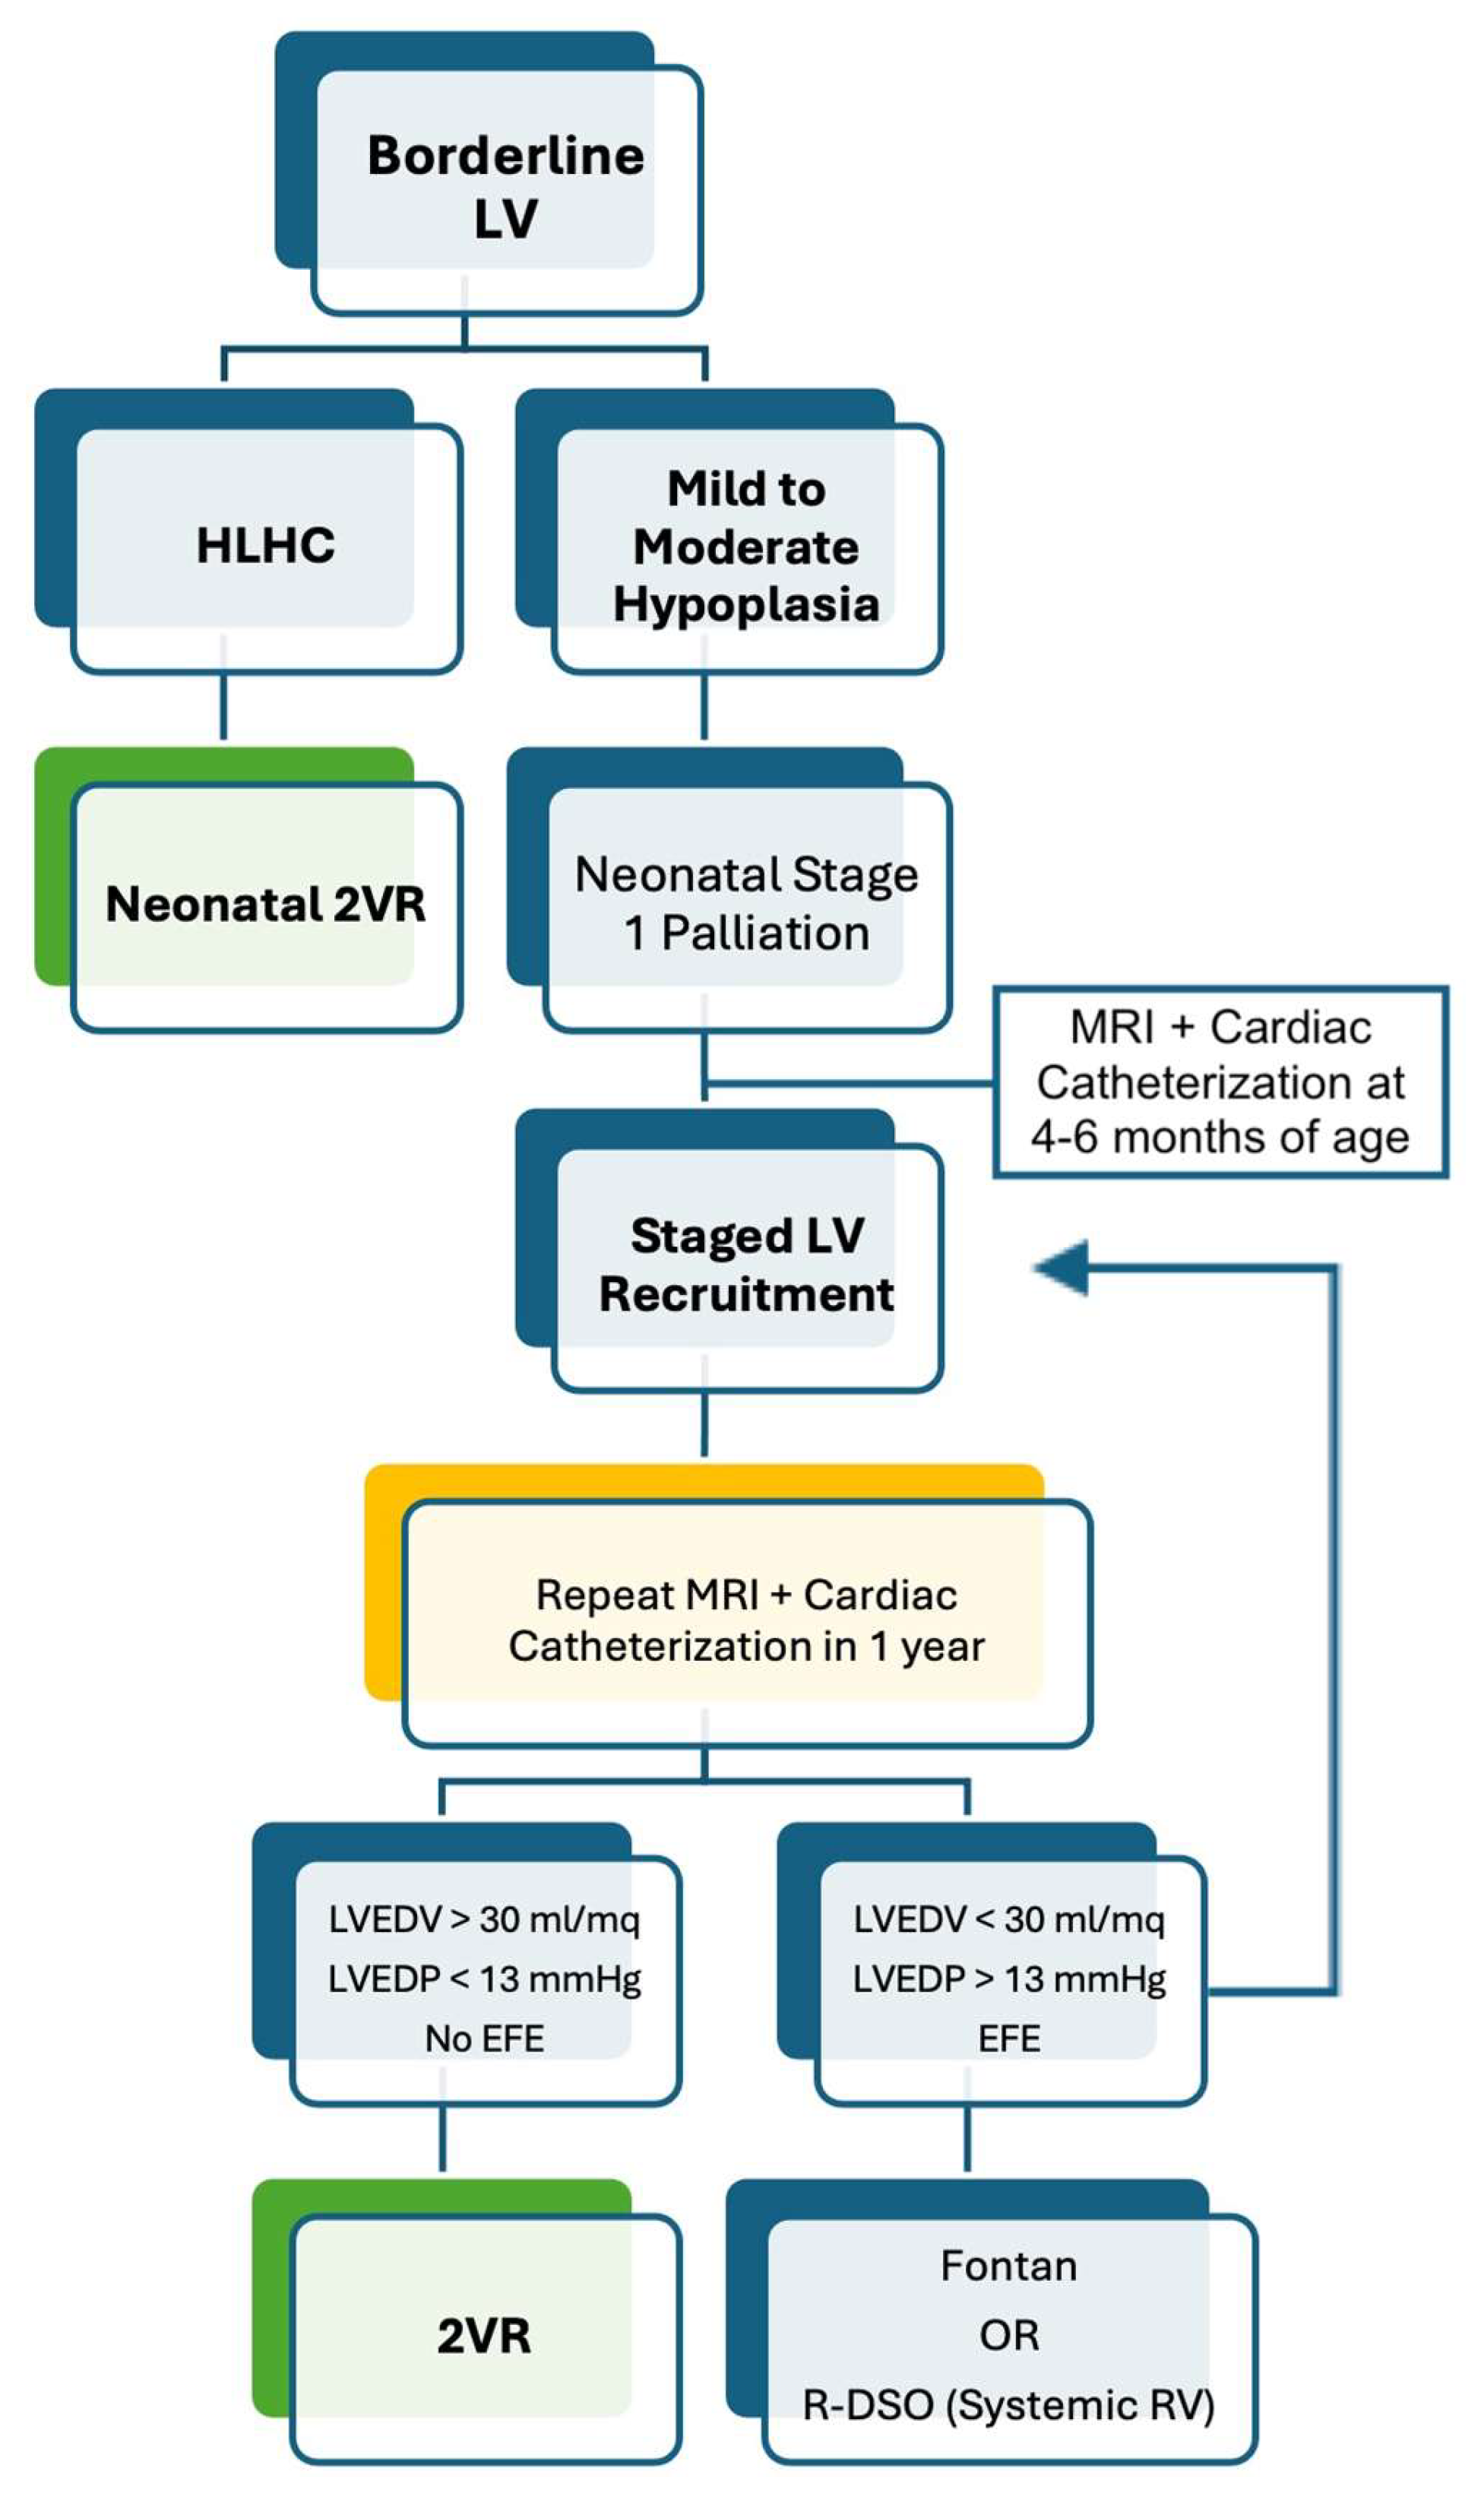

5.1. Borderline Left Ventricle

5.2. Borderline Right Ventricle

- Rhodes score (1991) [5]:

- CHSS equation (2001) [7]:

- Discriminant score (2006) [8]: